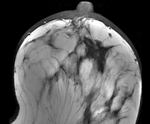

Registration Results

unregistered unregistered

affine registered affine

Bspline registered BSpline 9x9x4 max 15mm

Bspline registered Deformation field for BSpline 9x9x4 max 10mm

Bspline registered BSpline 7x7x5 max 10mm

After N4 bias correction and histogram equalization:

Bspline1 deformation only Deformation of Post image from unmasked BSpline 7x7x5 max 10mm

Bspline registered + tumor mask BSpline 7x7x5 max 10mm + tumor mask

Bspline1 deformation only Deformation of Post image from masked BSpline 7x7x5 max 10mm